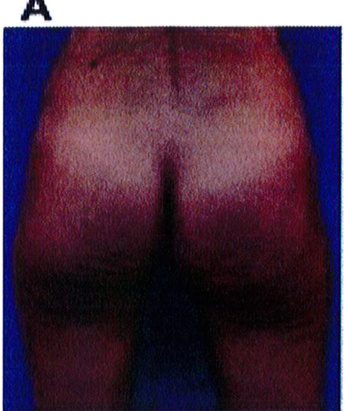

Hình. 18.. (A) Hình anh trước và (B) và sau phẫu thuật làm đầy mông của bệnh nhân được đặt khối implant dưới cân thể tích 225 mL, hai bên.

Bệnh nhân 31 tuổi tiền sử khỏe mạnh, có chỉ định nâng mông bằng implant do thiếu hụt thể tích. Hai khối anatomic implant 225 mL polyurethane dạng gel được đặt ở vị trí dưới cân. Sau phẫu thuật không ghi nhận biến chứng trong suốt quá trình hồi phục, vết mổ liền tốt (Hình 18).